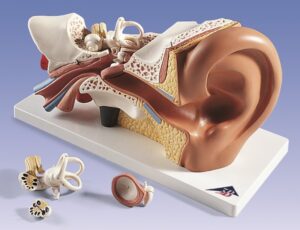

Ear Examination Simulator

UK 3B Scientific manufacture anatomical models and teaching aids for medical education. 3B Scientific manufacture Medical Simulators, Human anatomy models and charts for universities, schools & health boards.

With competitive value and quality products 3B Scientific equipment has become very popular. Their smart app and other advanced technologies allows students more anatomical information and learning than ever.